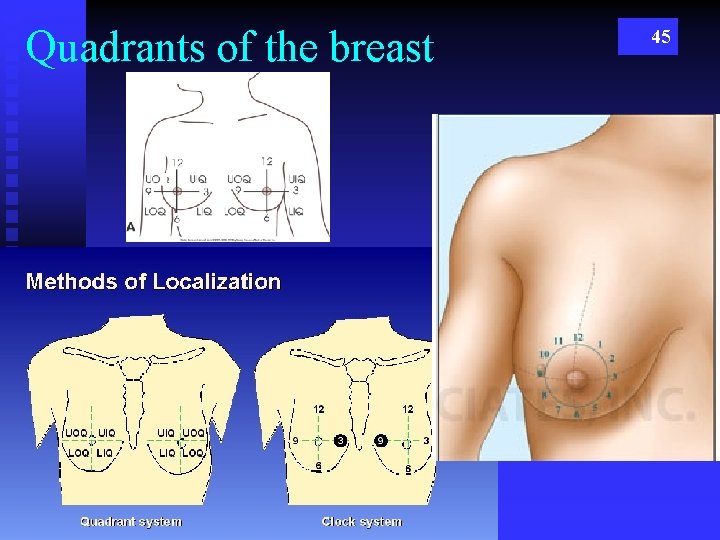

Quadrants of the breast 45